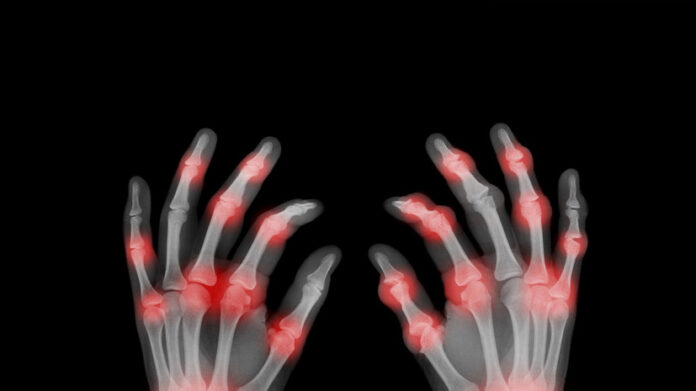

Ключевой задачей остаётся защита сердечно-сосудистой системы. Даже в сложных случаях, требующих хирургического вмешательства, инновационные методики демонстрируют высокую эффективность. Важно не пропустить тревожные сигналы: лихорадку, слабость, боль в суставах или нарушения сердечного ритма — их раннее распознавание открывает путь к полному восстановлению.